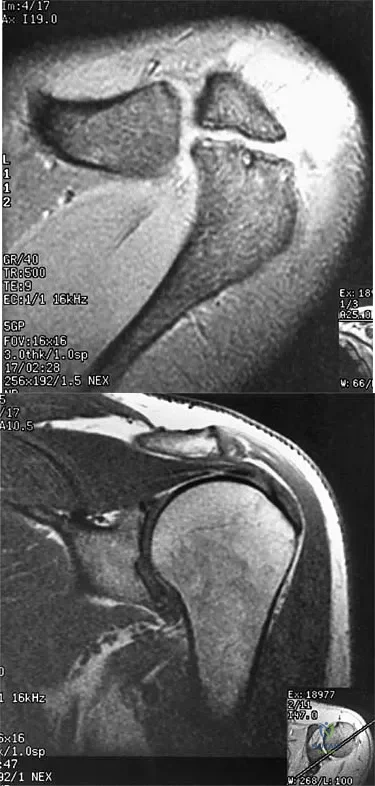

A right-handed 24-year-old professional baseball player injured his left shoulder 6 weeks ago when he dove forward and landed hard with the arm extended. He reports that the shoulder "slipped out" and "went back in." The shoulder did not need to be reduced. He now reports deep pain in the front of the shoulder when batting on either side and is hesitant to raise his left arm up over his head to catch a ball. Examination reveals no obvious deformities of the shoulder and a somewhat guarded, limited range of motion in all planes. Provocative tests for the rotator cuff and labrum are equivocal. MRI scans are shown in Figures 16a and 16b. What is the best course of action?

Explanation